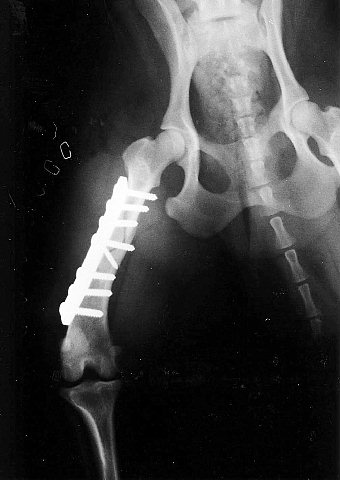

次は大腿骨の複雑骨折です。いわゆる「バラバラ」というわけです。

これは骨の破片を元の場所にネジで固定してから全体をプレートで固定します。